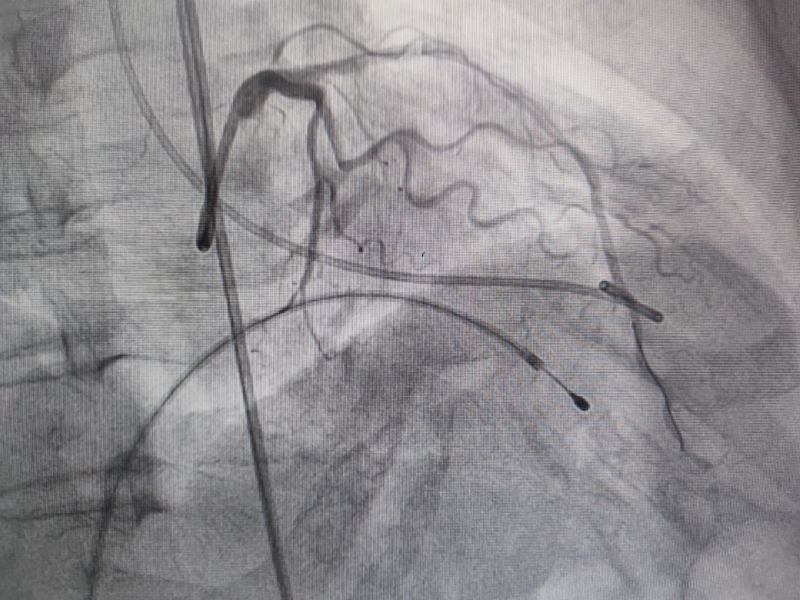

經(jīng)過多輪嚴(yán)謹(jǐn)?shù)男g(shù)前討論,在吳棟梁院長的專業(yè)指導(dǎo)下,崔旭輝主任醫(yī)師團(tuán)隊決定在臨時起搏器的安全保護(hù)下,為患者實施冠狀動脈造影術(shù)及室間隔化學(xué)消融術(shù)。術(shù)中,團(tuán)隊通過造影精準(zhǔn)鎖定第一穿隔支為消融靶血管。測壓數(shù)據(jù)顯示:左室壓260/15mmHg,流出道173/6mmHg,主動脈壓106/70 mmHg,壓力階差達(dá)87mmHg。隨后,團(tuán)隊使用2.0X15mm預(yù)擴(kuò)球囊以8atm壓力阻斷第一穿隔支遠(yuǎn)端血流1分鐘,再次測壓時,壓力從269/7mmHg驟降至174/4mmHg,這一結(jié)果充分證實該血管正是室間隔的有效供血血管。緊接著,團(tuán)隊通過SPRINTER OTW2.0×8mm球囊緩慢注入1.4ml無水酒精。10分鐘后復(fù)測,左心室壓降至136/5 mmHg,主動脈壓為112/93 mmHg。術(shù)后第2天,王女士胸悶、氣短、心悸等不適癥狀完全消失。復(fù)查心臟彩超顯示:EF值與FS值保持穩(wěn)定,收縮期左室流出道血流速度降至252cm/s,PG值為25mmHg。

消融后造影

測壓

消融時測壓